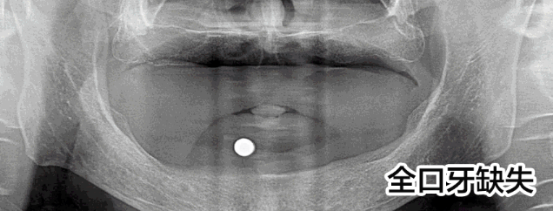

先天性牙缺失修復(fù)案例

趙先生先天性發(fā)育異常導(dǎo)致全口牙缺失,才36歲就掉了好幾顆牙,為此趙先生痛苦:“聽說這是一種病,發(fā)病概率小,但不知道怎么就被我攤上了。我還這么年輕就缺了這么多顆牙,真的很奔潰!”

趙先生的遭遇讓人同情,他尋找了多家醫(yī)院都被告知他由于牙齒缺失沒有進(jìn)行及時(shí)修復(fù)導(dǎo)致他的牙槽骨萎縮,再加上本身骨量不足,無(wú)法進(jìn)行牙齒種植。牙齒的問題讓趙先生一度有了輕生的念頭。而這次他通過新聞知道亞洲種植牙大師劉斌元教授來到福州,就抱著希望來到科爾。

劉斌元教授在為趙先生進(jìn)行一系列的檢查后說:“這位患者要做種植牙手術(shù)的話的確復(fù)雜,但是也并非說不能種植,就是操作起來難度大。”

趙先生的手術(shù)順利,種植牙齒后他覺得整個(gè)人都活過來了。

“當(dāng)時(shí)只是覺得人很舒服,一下子就放松了,之后腦子就是一片空白,手術(shù)進(jìn)行的很快,從進(jìn)入種植間到至后一顆種植牙的植入,只用了短短3個(gè)小時(shí)”,三分鐘改變了趙先生的一生,趙先生感激劉斌元教授:“如果沒有劉斌元教授為我進(jìn)行手術(shù),我都不知道接下來該怎么辦?,F(xiàn)在說什么都不能表達(dá)我的感激之情,但還是要對(duì)劉院長(zhǎng)說一聲謝謝!”

首先,像趙先生這樣的先天性發(fā)育不良造成的全口牙缺失的病例本身就是很罕見的,可以說是幾十年難遇。其次,全口牙缺失本身就屬于牙科領(lǐng)域中難的一種技術(shù)。沒有先進(jìn)的高精口腔CT技術(shù)的保障,在傳統(tǒng)的診療條件下,很難手術(shù)的。因而,在硬件、設(shè)備、技術(shù)還不成熟的情況下,并不是所有醫(yī)院都能完成這種病例的調(diào)節(jié)。因此,在做全口牙種植前,選擇正規(guī)的醫(yī)院和臨床經(jīng)驗(yàn)豐富的醫(yī)生,是保障手術(shù)成功的先決條件。